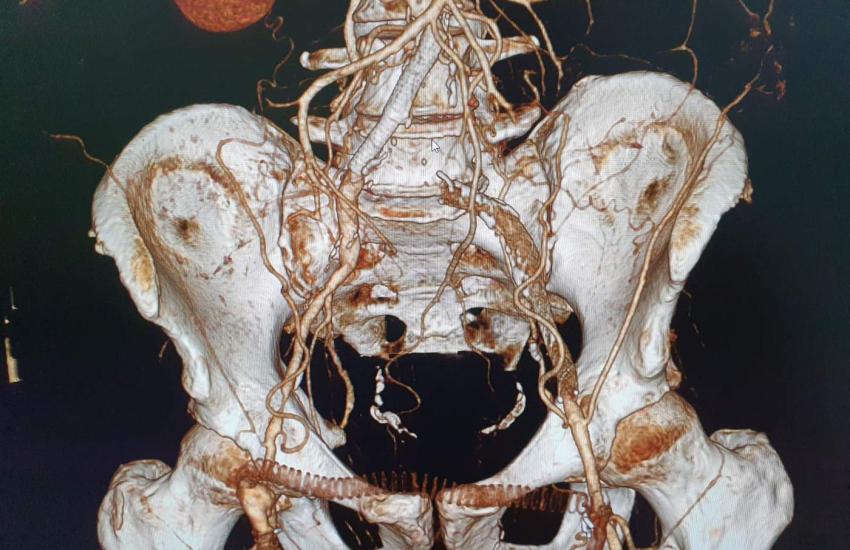

На базі відділення інтервенційної радіології КНП «Черкаська обласна лікарня Черкаської обласної ради» в.о. завідувачем відділення інтервенційної радіології Дмитром Паляничко разом з колегою Святославом Денисовим завідувачем відділення ендоваскулярної хірургії Клінічної лікарні «Феофанія» успішно проведена унікальна чотирьох годинна ендоваскулярна малоінвазивна операція з приводу тромбозу біфуркації аорти.

До Черкаської обласної лікарні поступив пацієнт з діагнозом: тромбоз загальної клубової артерії зліва. Хвороба небезпечна та потребувала оперативного втручання, інакше – пацієнт з високою ймовірністю міг втратити нижню кінцівку. Лікарі розглянули дві альтернативи – ендоваскулярна малоінвазивна операція або відкрита операція. Перевага була надана першому варіанту, оскільки відкрита операція потребувала б великих розрізів, крововтрат, значного травмування тканин та тривалого післяопераційного відновлення.

Під час операції був використаний пристрій Ratarex (Швейцарія), видалені тромботичні маси та проведено біфукарційне стентування. Крововтрата операції становила до 50 мл. А головне, збережена нижня кінцівка, і пацієнт уникнув інвалідизації. Вже через добу після операції він почав самостійно ходити та наразі почуває себе добре.